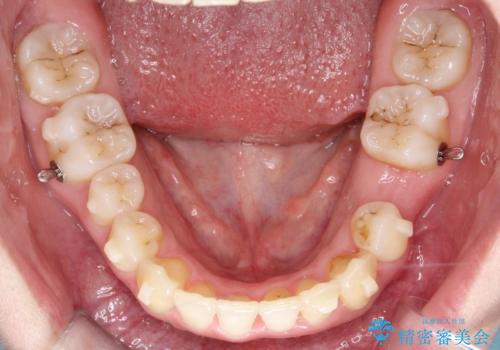

前歯のガタガタと欠損部を改善

- 患者様は、前歯のガタガタ(叢生)と左下5番の欠損部が気になるとのことで来院されました。診断の結果、インビザラインを用いて前歯の叢生を整えながら、左下5番の欠損部にはインプラント治療を計画しました。矯正治療により、歯並びを改善すると同時に、噛み合わせのバランスも向上させることを目標としました。矯正期間とインプラントの治療計画を並行して進めることで、患者様のご希望に応えるプランを立てました。

前歯の叢生改善のため、インビザラインによる透明で目立たない矯正装置を使用しました。治療中は、歯の移動による負担を最小限に抑えつつ、歯列全体のバランスを考慮して進めました。左下5番の欠損部には、矯正終了後にインプラントを埋入し、自然で機能的な咬合を回復しました。治療期間中、患者様には装置の正しい装着と日々の清掃を徹底していただき、歯肉やインプラント周囲の健康を保つようサポートしました。結果として、美しい歯並びと快適な噛み合わせを両立させることができました。